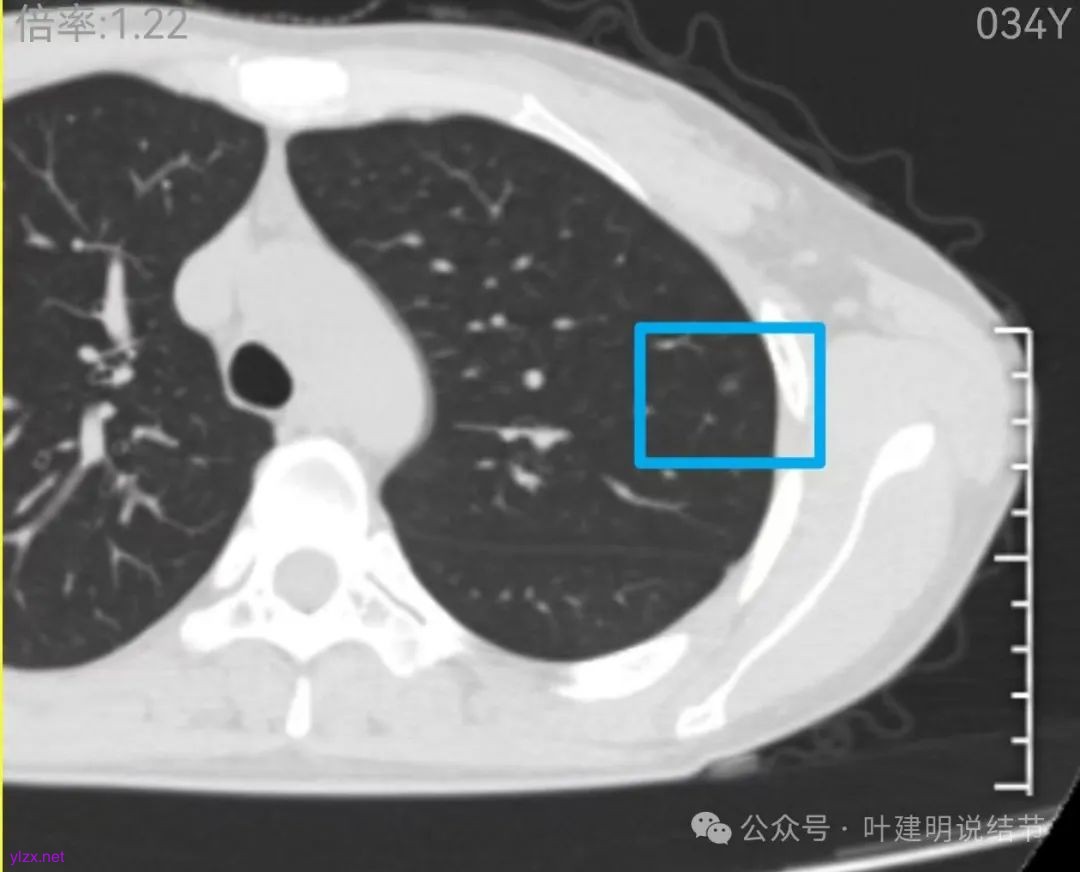

两肺多发结节,左侧黄色标注的考虑是肺泡上皮增生可能性大;蓝色的考虑肺泡上皮增生或者少许慢性炎可能性大;右侧红色宽起来并带有红色箭头的这处是主病灶,偏混合密度,整体轮廓较为清楚,边缘显得毛糙,从2024年12月份的来看,要考虑是肿瘤范畴,原位癌或者微浸润性腺癌可能性较大,也不能完全排除不典型增生。但是在2022年的时候,这个病灶的边上也有一个实性的微小结节,如果只看2022年的,这么小的实性结节,又比较圆,表面也显得较为光滑,是要考虑良性的,当然太小了需要动态观察。回头再重新来看2024年底的,发现绿色箭头所指的这个微小实性的较2022年几乎没有变,去仔细寻找2022年的,发现当时在实性结节旁边也有密度很淡的一点磨玻璃影(也可能真的就是一处,只是扫描不够薄,密度的变化有些突兀而已),而到了2024年12月份,实性微小这处没有明显变化,但是原来很淡的磨玻璃变成了混合磨玻璃,范围也明显扩大。所以总体来看右肺下叶这处是考虑恶性的,而且从磨玻璃结节角度来讲,还是生长比较快的,就是说还是有一定风险的。加上左侧还有两处也是磨玻璃持续存在,虽然边缘轮廓显模糊一点,但多年以后也可能仍然要变成原位癌或者微浸润性腺癌之类的东西。通盘考虑以后,我倾向于右侧近期单孔胸腔镜下微创局部切除,左侧随访观察,等到有进展并风险增加再来考虑处理。意见供参考!

左肺尖病灶当时也有,没有明显变化。

左上叶此处当时也有,只是没有2024年轮廓与边界那么清楚,而且范围也是当时小点的。

左肺尖病灶相仿。

左上此灶2023攫与2022年时均较小,范围在2024年略有增大,显明显点。